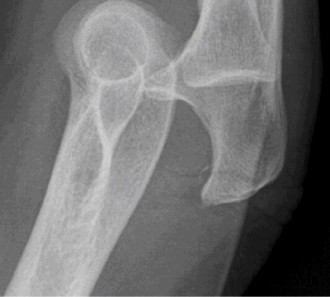

A 32-year-old male presented to the emergency department 1 hour after sustaining a fall while skateboarding. The patient complained of pain in the elbow with swelling and deformity present. He denied numbness or tingling.

Examination reveals deformity about the elbow with no open lesions or skin tenting. He has a palpable radial and ulnar pulse and is neurologically intact. His images are shown (Figs. 2–85 to 2–88).

Figure 2–85

The correct answer is (B). This is the most common type of elbow dislocation, and often does not cause any osseous injury. Posterolateral and posteromedial dislocation account for approximately 90% of dislocations. Adequate pre- and postreduction films are necessary to evaluate for fracture, which would change the classification to a complex injury.